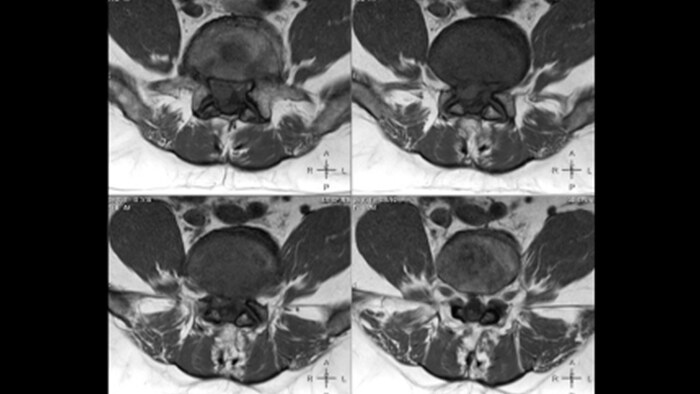

In addition to installation cost, also the longevity, reliability and lifetime cost of the MRI were factors influencing Dr. Mahajan’s purchase decision. “With Prodiva 1.5T we were getting a highend system at a reasonable price, and because it includes latest technology I expect a long lifetime of the system,” he says. “The low power use of Prodiva helps to keep our energy cost low. We have already experienced that the power requirement is much less than it is for other MRI scanners. We used to need up to 120 kVA, but for Prodiva this number is down to 50 kVA, so even there we find cost savings.” Dr. Mahajan notes that “some of the other major considerations are the quality of the service and the frequencies of breakdowns.” He and his staff appreciate the high amount of uptime they experience with the Prodiva system. “There have haven’t been any significant breakdowns in the past 16 months since we have had the machine, so we never had to send a patient away because the machine was down.” The flexibility gained by using the Prodiva flexible phased array MSK coils also brings down the price of imaging, according to Dr. Mahajan. Previously, each had a dedicated coil. “I have always bought dedicated coils for every joint and body part, which is no longer necessary. Prodiva’s smaller digital MSK coils can be combined to become larger coils. By fitting them together, we can image both small and large body parts using the same equipment.”

“The flexible digital MSK coils felt like a revolution: we can use them in any plane we want: longitudinal, horizontally, or vertically, and they function,” says Dr. Mahajan. “These flexible coils allow for imaging a smaller FOV with one coil, and larger FOV with multiple coils in tandem. In some exams, for instance thigh and leg, techs don’t need to move the coils during scanning anymore, which offers a versatility which was never possible with any other coils. Use of these coils also allows for whole body imaging, with imaging coverage of 190 cm with 50 x 50 x 45 cm field of view (FOV).”

Obtaining high quality imaging in a broad group of patients requires dealing with factors that may impact image quality. Prodiva offers some powerful tools to help reduce artifacts that can potentially hamper diagnostic confidence or lead to repeat scans. “Movement, however minor, creates artifacts on images. Fortunately, MultiVane XD reduces motion artifacts, which helps us very much with patients who are less cooperative or who are semi-conscious, as well as patients with stroke.” “The method that Prodiva 1.5T offers for reducing the artifacts caused by metal also works very well, both in the extremities around implants as well as in the spine. In order to obtain robust, uniform fat suppression we can use the mDIXON fat suppression, which is especially helpful in the extremities and in whole body imaging.”

In this patient MRI images show spondylotic degenerative changes in the lumbar spine, in view of the osteophyte, disc desiccations and Sc hmorl’s nodes with lumbarization of S1, post-laminectomy changes at L5-S1 and S1-S2 levels with disc protrusion and extrusion, and diffuse disc bulges from L3-L5 with nerve root compression.